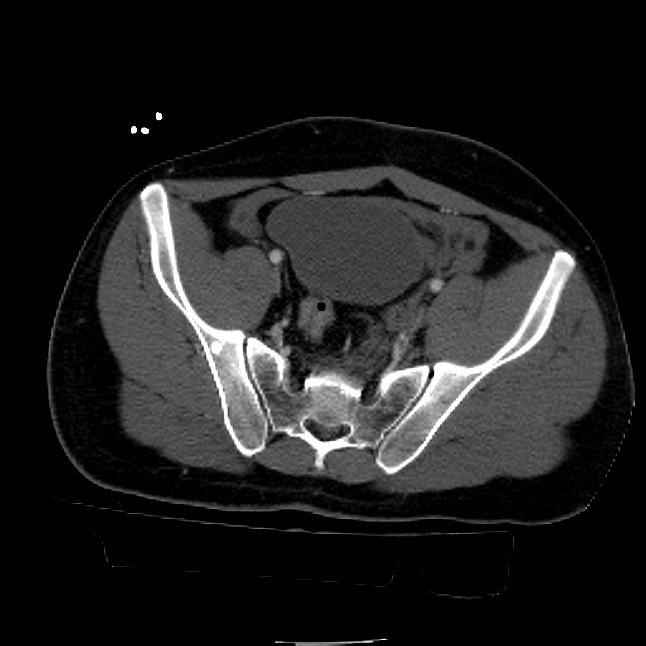

25 yo brittle diabetic, became hypoglycemic and passed out on his motorcycle. Sustained bilateral lateral Hoffa fractures with associated LCL injury on the right and right distal radius fracture. I have questions regarding his pelvic ring/acetabular fracture on the left. Appears to be a very low posterior column fracture with associated posterior wall, marginal impaction. Superior and inferior rami fractures as well on the left giving him a floating segment of inf ramus/ischium/posterior column, but no detectable posterior ring injury. Should the posterior column/posterior wall fracture be addressed surgically because of the marginal impaction? Or is this fracture low enough to be treated non-operatively? I appreciate the input.

It's an interesting case. The plain films show the impaction, but most of the joint looks pretty good. The CT cuts look awful, though.

The impaction is so big I don't think I would ignore it. It IS down low, but it takes up almost the whole southern hemisphere of his joint.